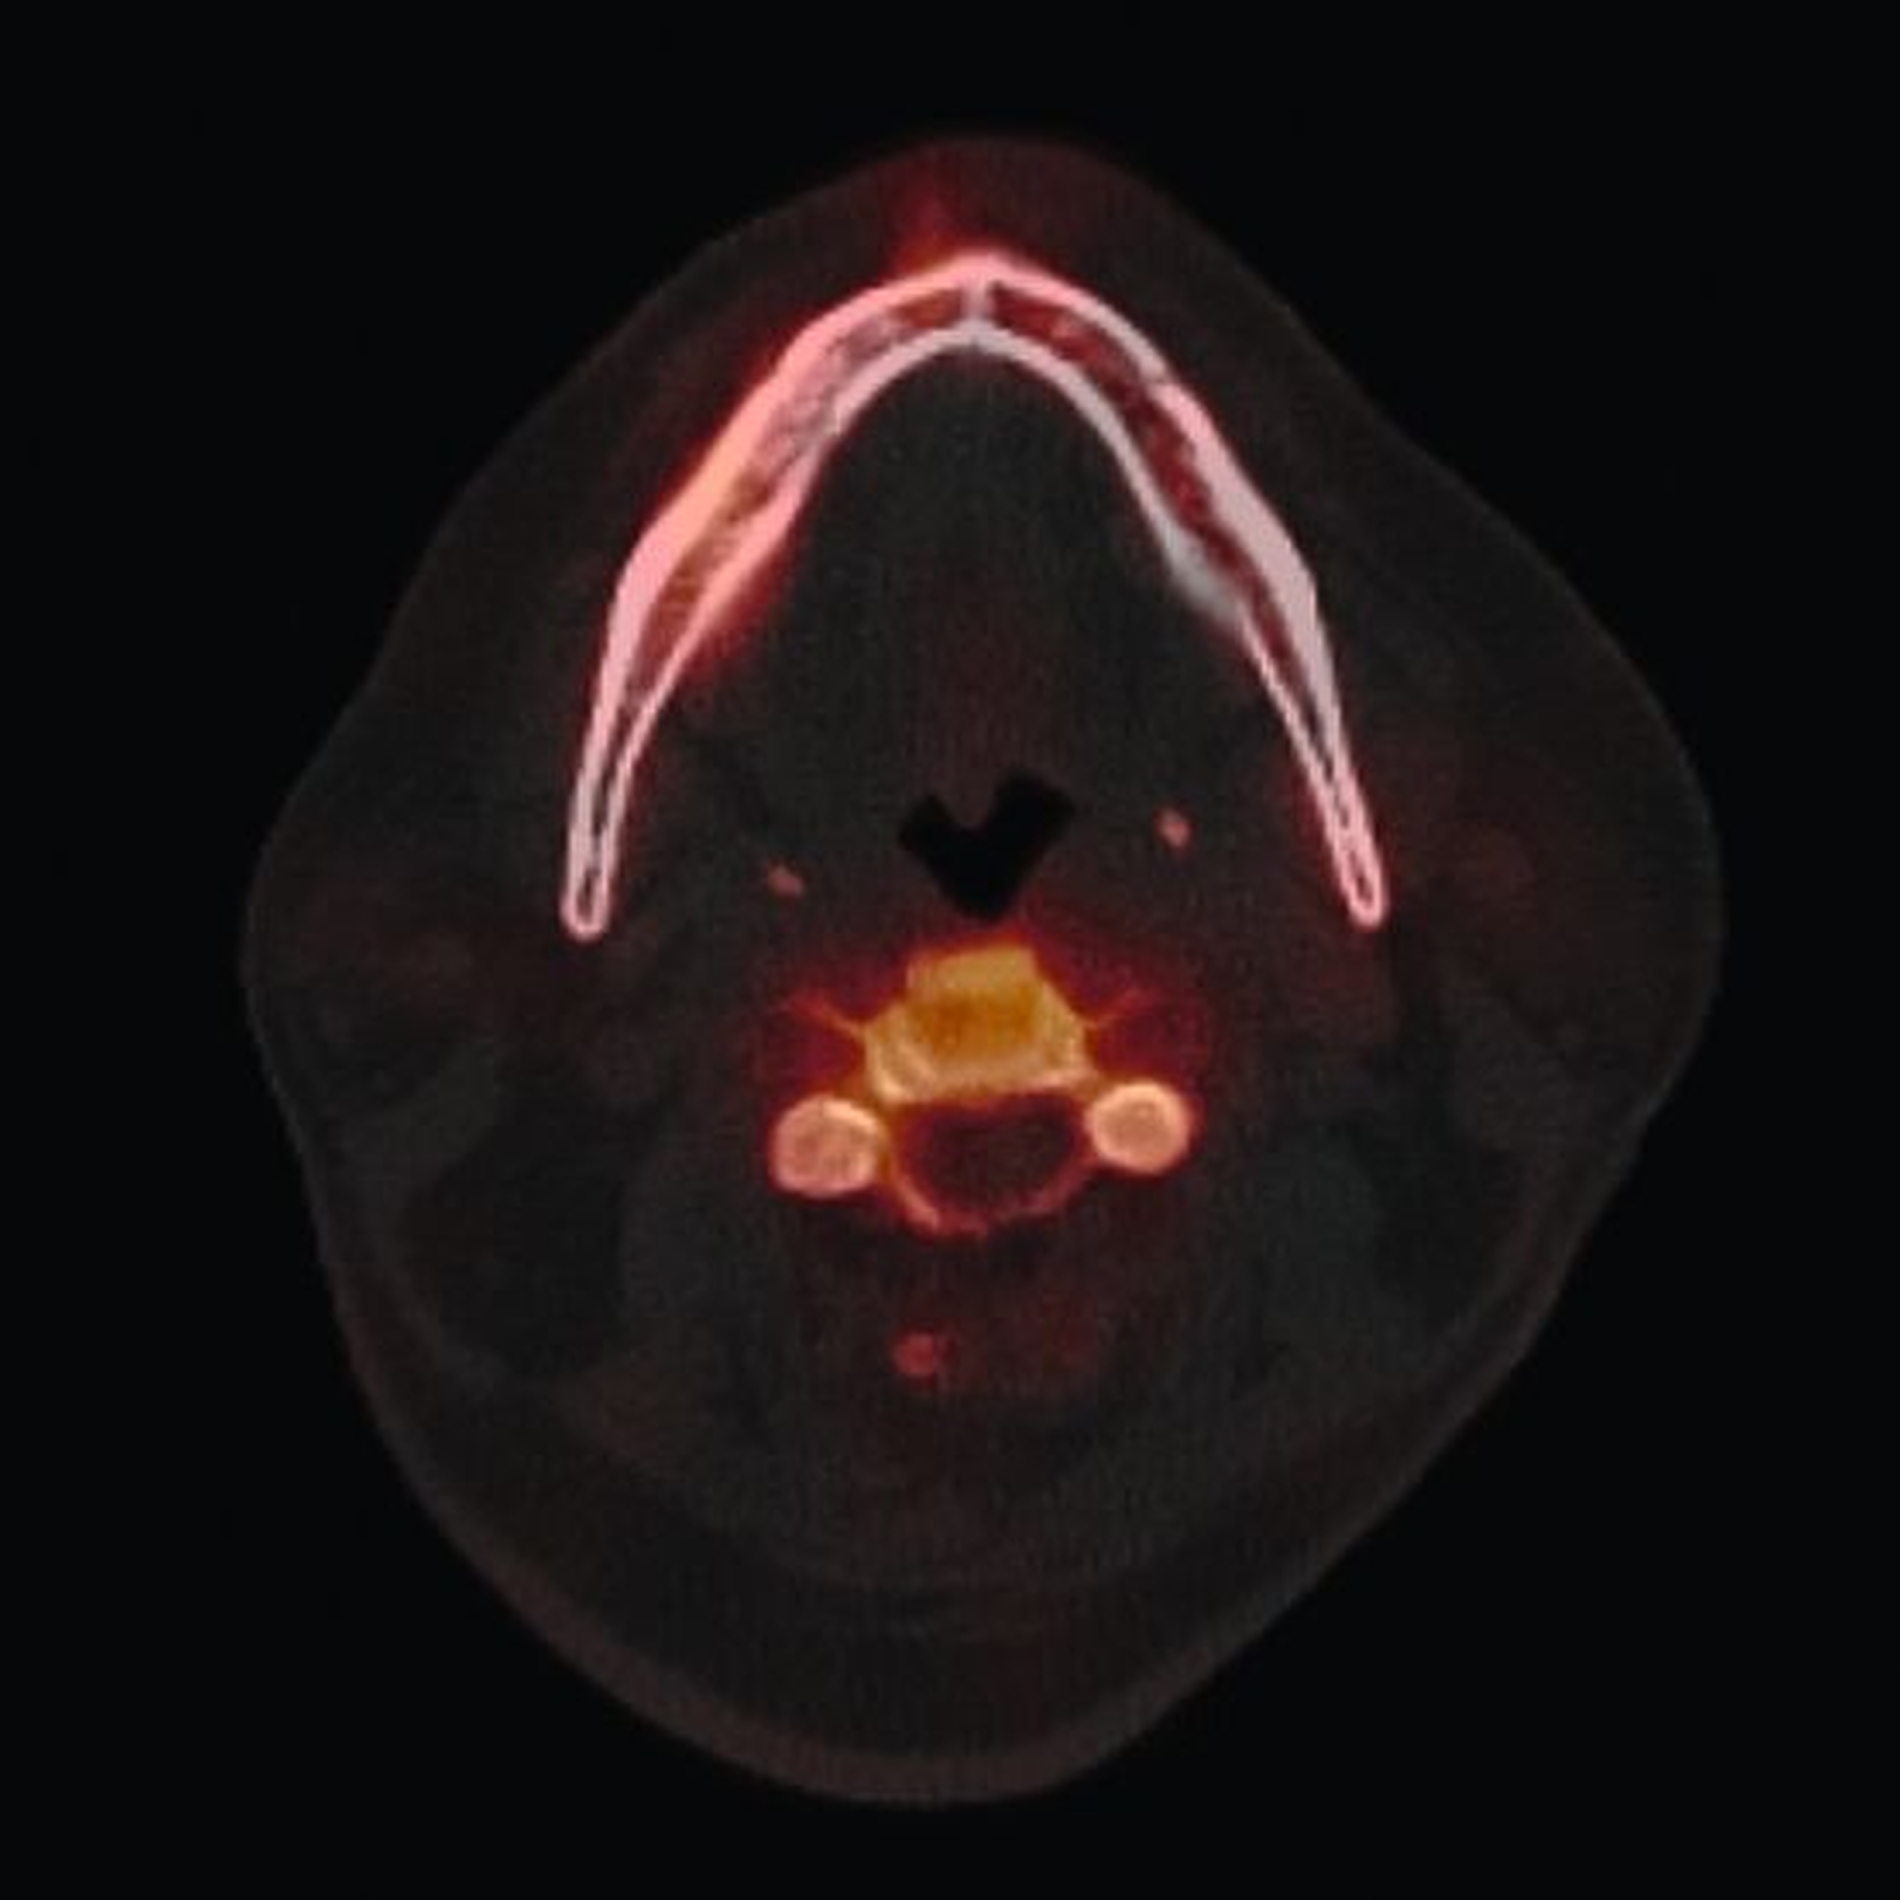

Zum Zeitpunkt der Erstvorstellung in der kieferchirurgischen Ambulanz zeigten sich keine klassischen Herpes-Zoster-Effloreszenzen im Gesicht. Eine antiresorptive Therapie oder Bestrahlung lag nicht vor, sodass eine Herpes-Zoster-assoziierte Osteonekrose im Sinne einer Ausschlussdiagnose festgestellt wurde. Anamnestisch bestand ein gut eingestellter Diabetes mellitus Typ 2 als potenziell immunkompromittierende Grunderkrankung. Die Knochenszintigrafie zeigte eine deutliche Stoffwechselsteigerung im betroffenen Bereich, vereinbar mit einer infizierten Osteonekrose.

Die Knochenszintigrafie zeigte in diesem Fall eine deutliche lokale Mehranreicherung, wie man sie in vergleichbarer Intensität auch bei Medikamenten-assoziierten oder Strahlenbedingten Osteonekrosen beobachten kann. Während bei diesen Entitäten aufgrund der chronischen Ischämie meist ausgedehnte, teils kontinuitätunterbrechende Resektionen erforderlich sind, unterscheidet sich die Pathophysiologie der Herpes-Zoster-assoziierten Osteonekrose grundlegend. Da hier eine vorübergehende, Virus-induzierte Vaskulitis vorliegt, sollte die szintigrafische Aktivität nicht überinterpretiert, sondern ein zurückhaltendes, reduziert-invasives chirurgisches Vorgehen gewählt werden. Der beschriebene Heilungsverlauf bestätigt die Effektivität des gewählten konservativen Vorgehens.